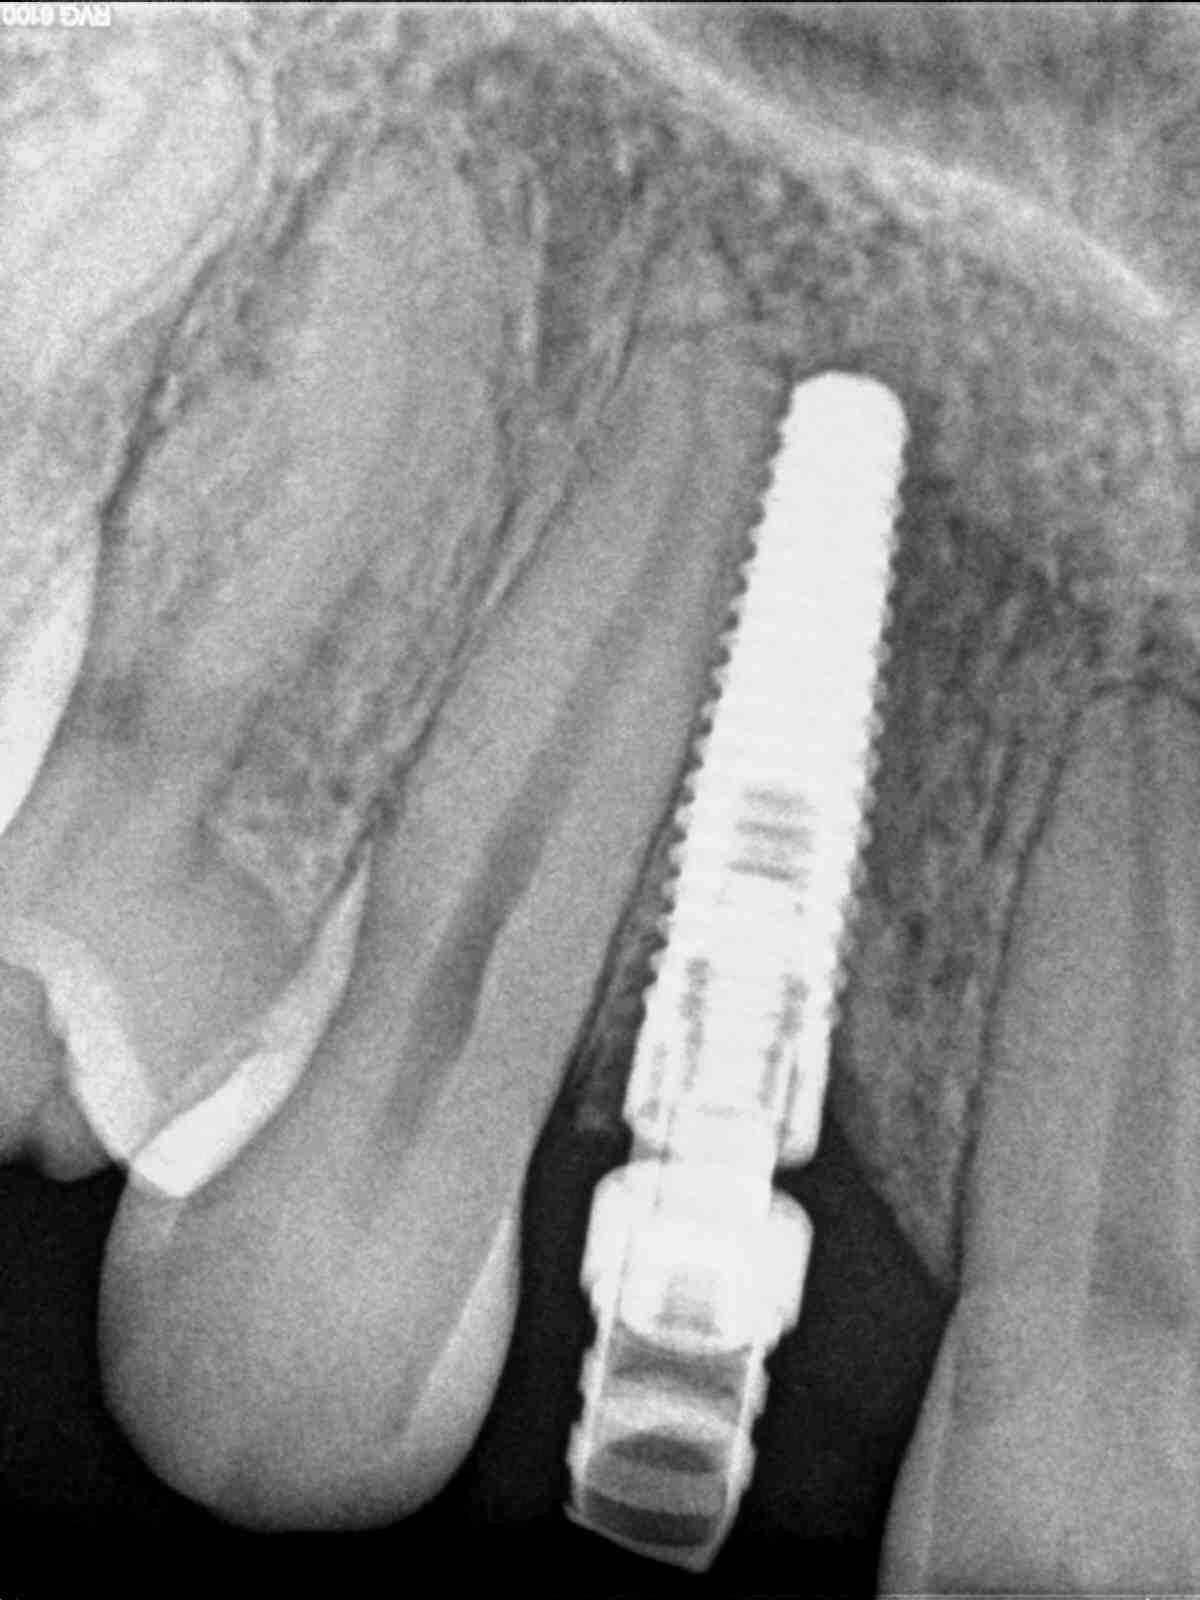

J'ai récuperer ce patient avec un implant que je pense être un NobelReplace Tapered Groovy NP 3.5 x 13mm à confirmer: il est posé plus ou moins l'emergence est correcte donc

çà semble être bien un Nobel...

P.S: c'est une provisoire sur l'implant?...il y a comme un problème de mise en place du pilier...c'est pas à fond...

> P.S: c'est une provisoire sur l'implant?...il y a comme un problème de mise en

> place du pilier...c'est pas à fond...